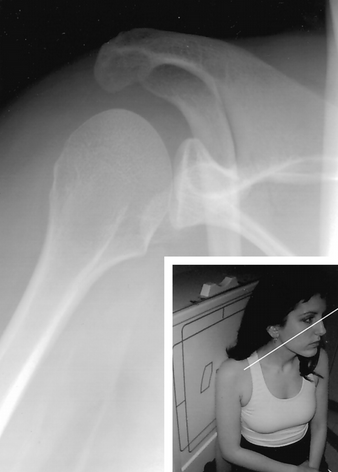

How do you do a Garth View

what are you looking for?

Apical oblique

patient is seated with the arm at the side;

Looking for anterior bankart

How do you do a True AP of shoulder?

Taken 30-40 degrees oblique to the coronal plane of the body

What is a Grashey view?

true AP of GH